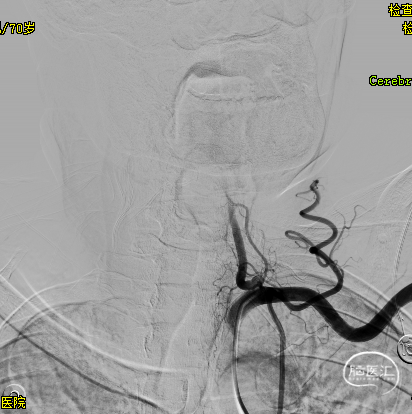

➢2024.07.09 入院急诊DSA:

造影见基底动脉中下段急性闭塞

造影见左侧优势椎动脉血流减慢

右侧椎动脉慢性闭塞

左侧颈内动脉无代偿

右侧后交通开放